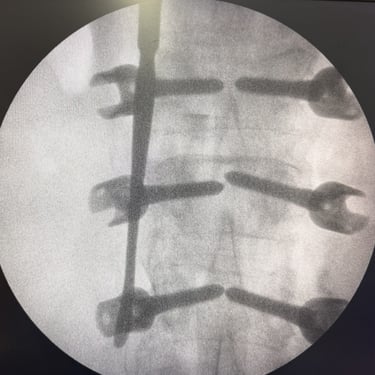

🧠Listesis Lumbar L5–S1 por Fractura Ístmica: Estabilización con FTP y TLIF.

La listesis L5–S1 por fractura ístmica causa inestabilidad y dolor. El tratamiento quirúrgico con FTP y TLIF permite descompresión neural y estabilización vertebral, mejorando la función y calidad de vida.